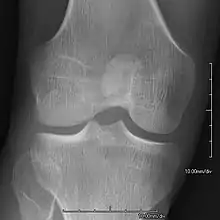

- Patellar involvement is present in approximately 90% of patients; however, patellar aplasia occurs in only 20%.

- In instances in which the patellae are smaller or luxated, the knees may be unstable.

- Exostoses arising from the posterior aspect of the iliac bones ("iliac horns") are present in as many as 80% of patients; this finding is considered pathognomonic for the syndrome.

An elbow of a man with nail–patella syndrome (NPS)